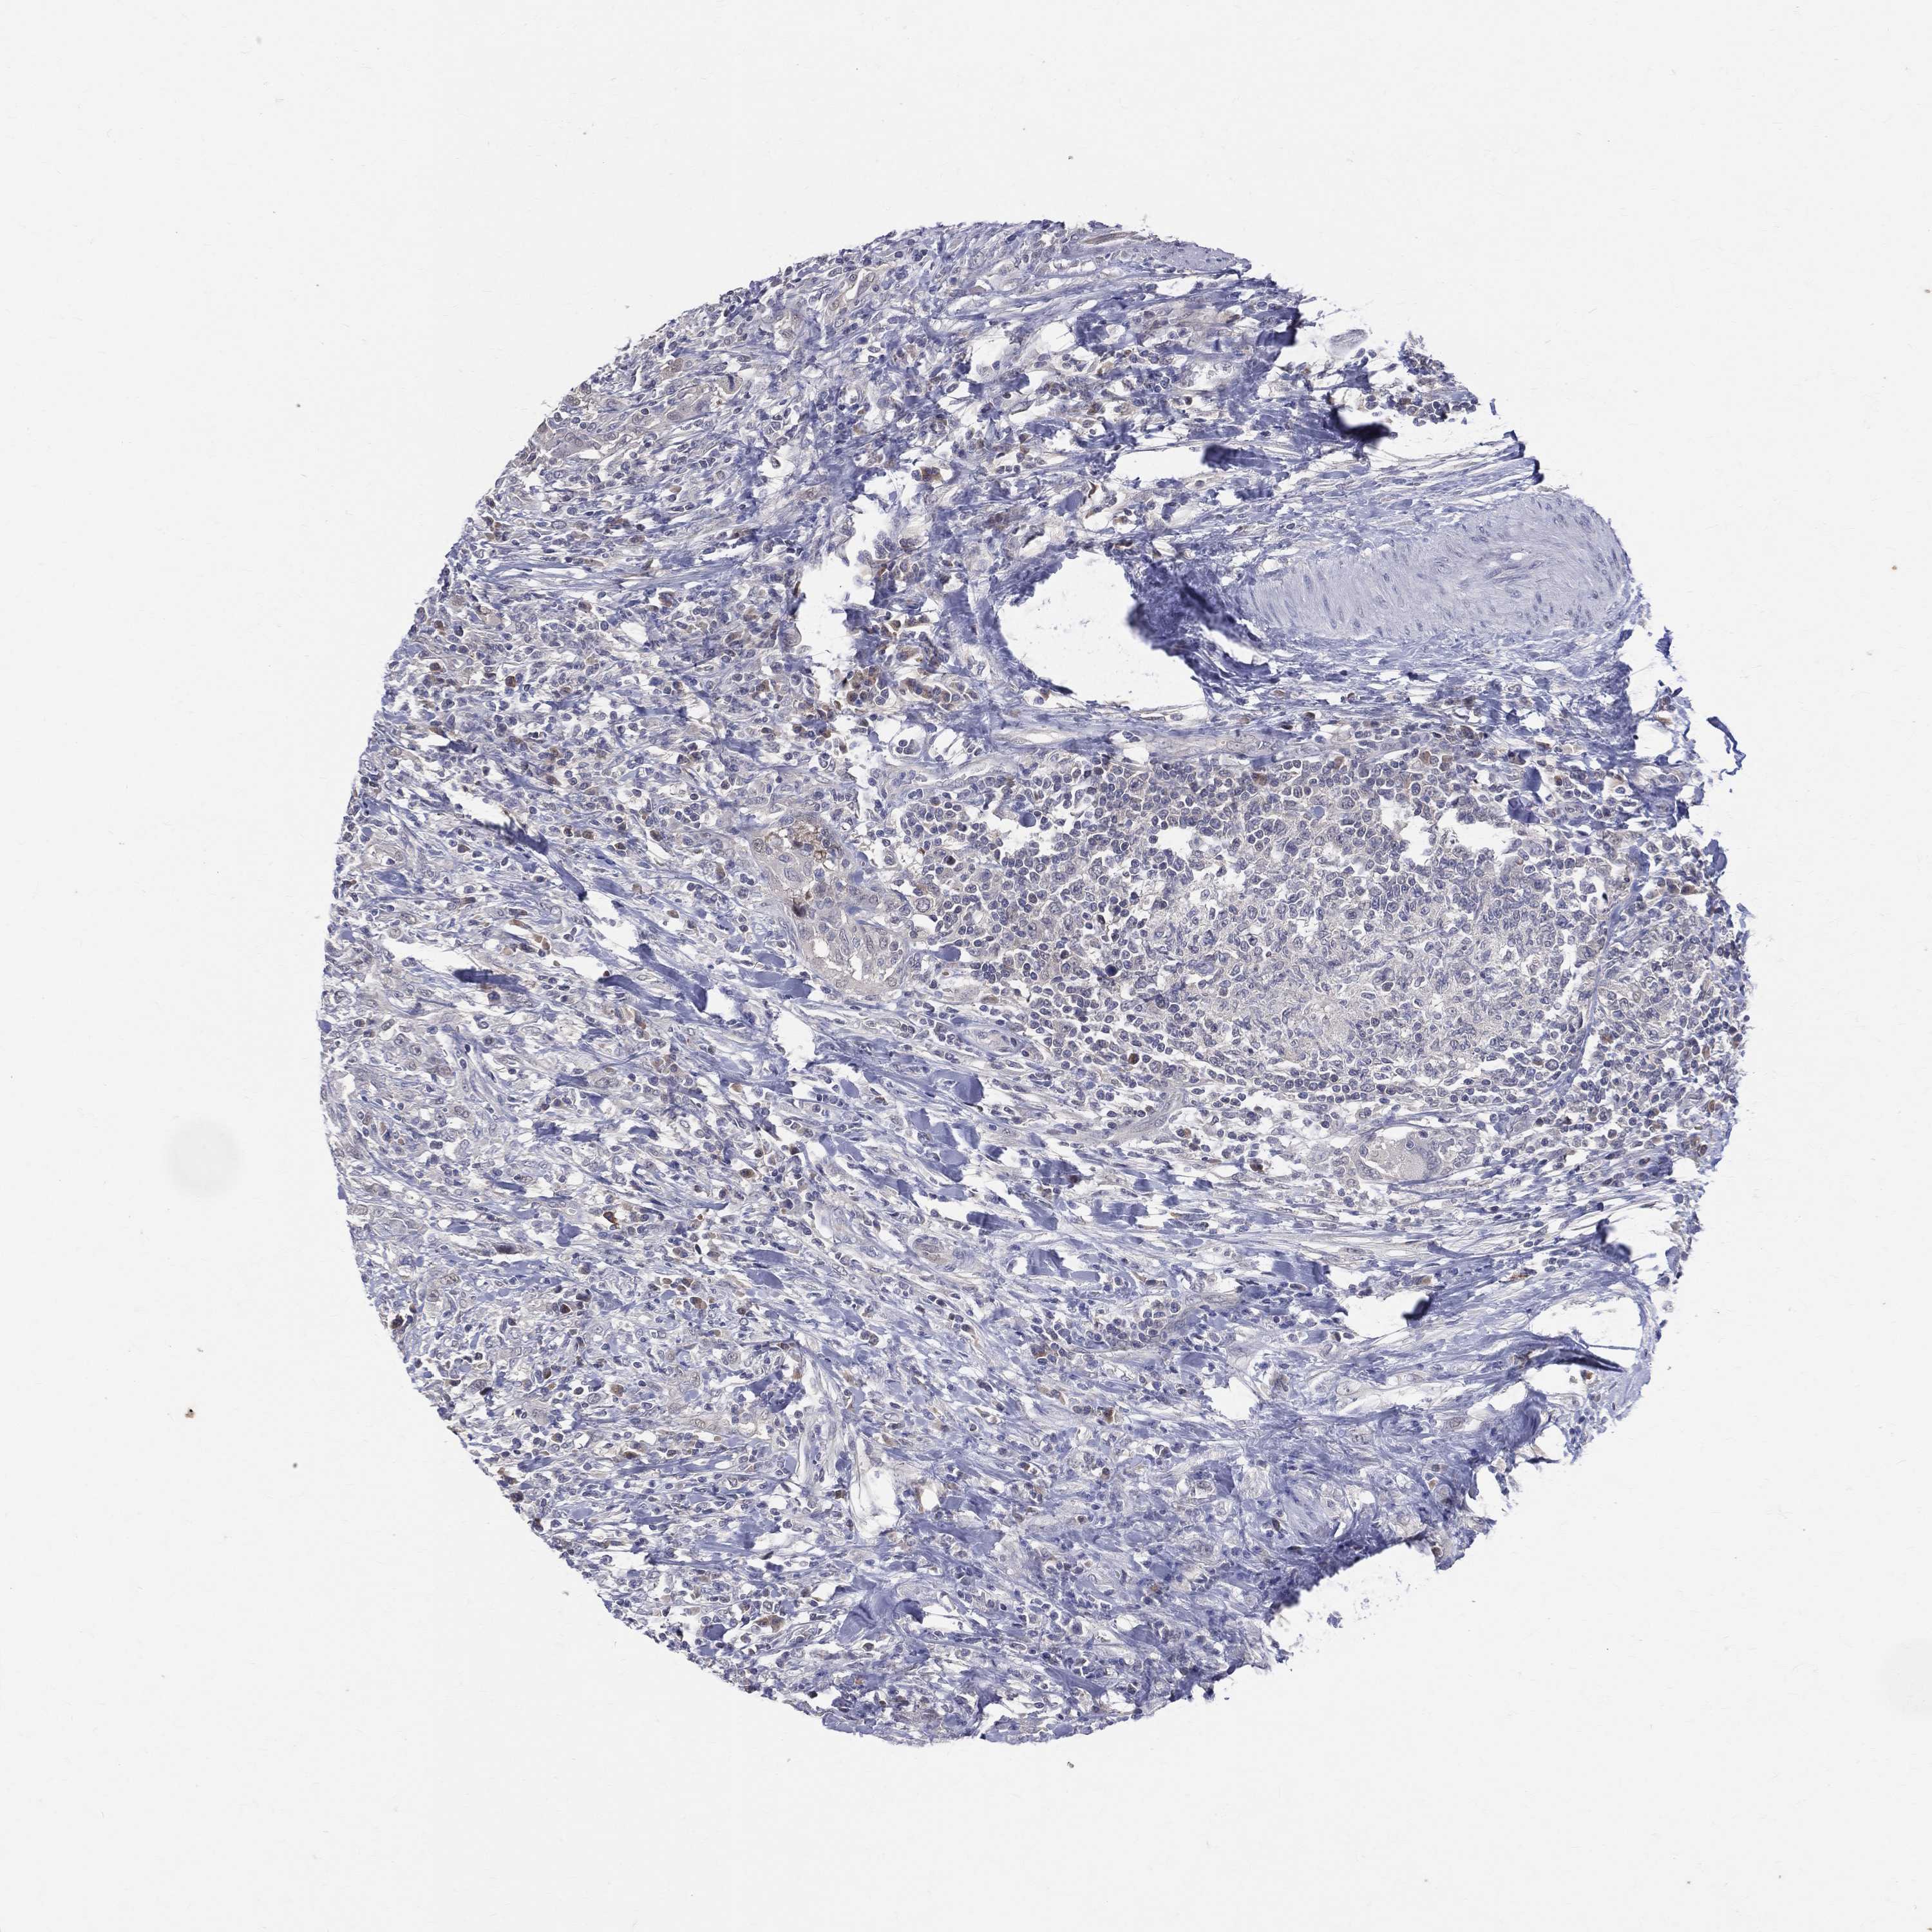

UROTHELIAL CANCER - Protein expressioni

A mouse-over function shows sample information and annotation data. Click on an image to view it in a full screen mode. Samples can be filtered based on level of antibody staining by selecting one or several of the following categories: high, medium, low and not detected. The assay and annotation is described here.

Note that samples used for immunohistochemistry by the Human Protein Atlas do not correspond to samples in the TCGA dataset.

Antibody stainingi

Antibody staining in the annotated cell types in the current human tissue is reported as not detected, low, medium, or high, based on conventional immunohistochemistry profiling in selected tissues. This score is based on the combination of the staining intensity and fraction of stained cells.

Each image is clickable and will lead to virtual microscopy that enables deeper exploration of all samples and also displays staining intensity scores, fraction scores and subcellular localization as well as patient and tissue information for each sample.

Antibody HPA010122

Antibody HPA071006

Antibody CAB001999

Antibody CAB002000

Staining

High

Medium

Low

Not detected

Intensity

Strong

Moderate

Weak

Negative

Quantity

>75%

75%-25%

<25%

None

Location

Nuclear

Cytoplasmic/membranous

Cytoplasmic/membranous,nuclear

Urothelial carcinoma, Low grade

Urothelial carcinoma, High grade

Urothelial carcinoma, NOS

Adenocarcinoma, NOS